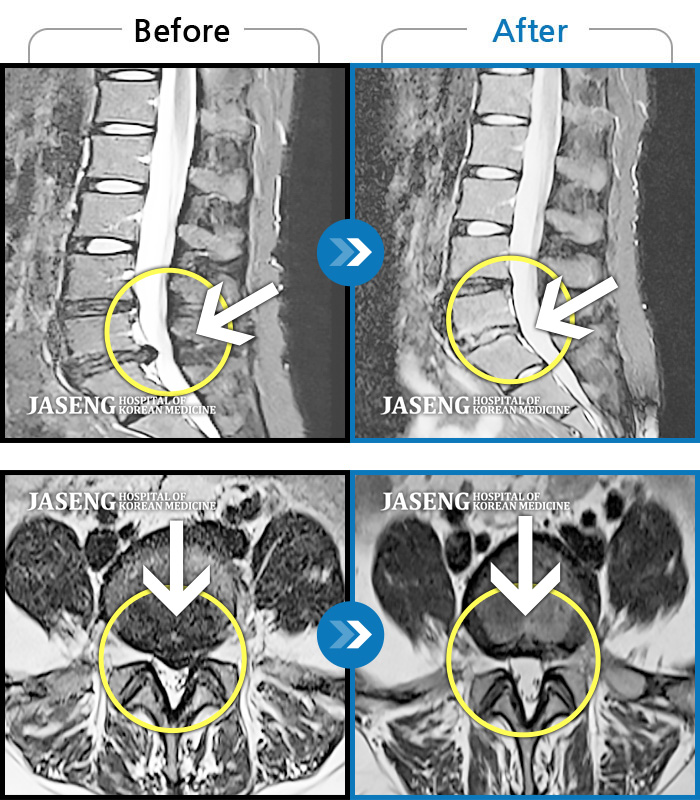

Before

After

환자에게 사전 동의를 받아 동일 조건에서 촬영되었습니다.

개인에 따라 치료 후 부작용이 발생할 수 있으니 의료진과 상담 후 치료를 진행하시기 바랍니다.